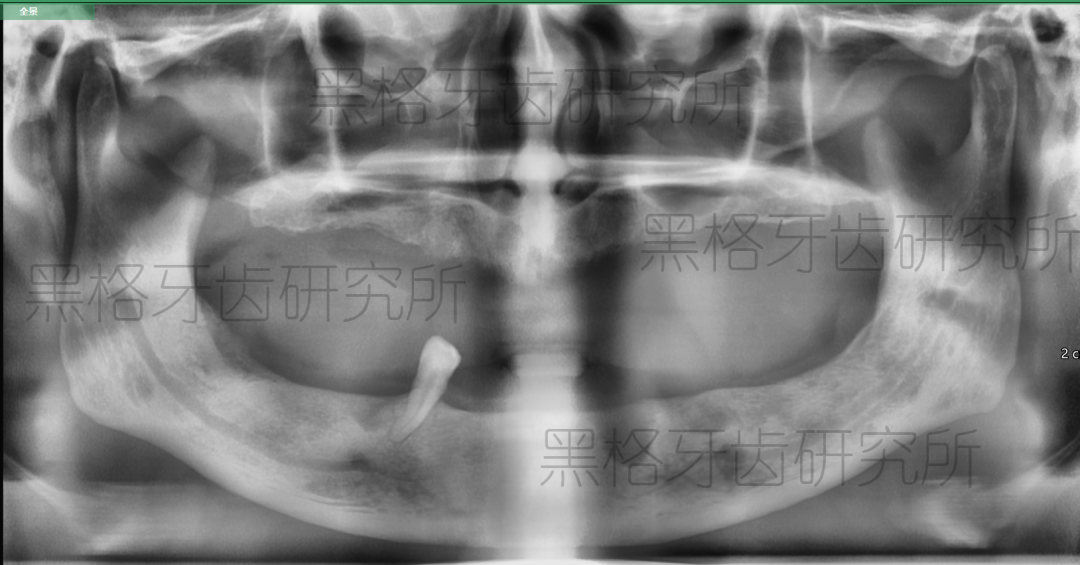

梁阿伯的牙片,因沒有刷牙習(xí)慣,患上牙周炎,牙齒全部脫落,目前僅剩一顆自然牙

梁阿伯種植后牙片展示